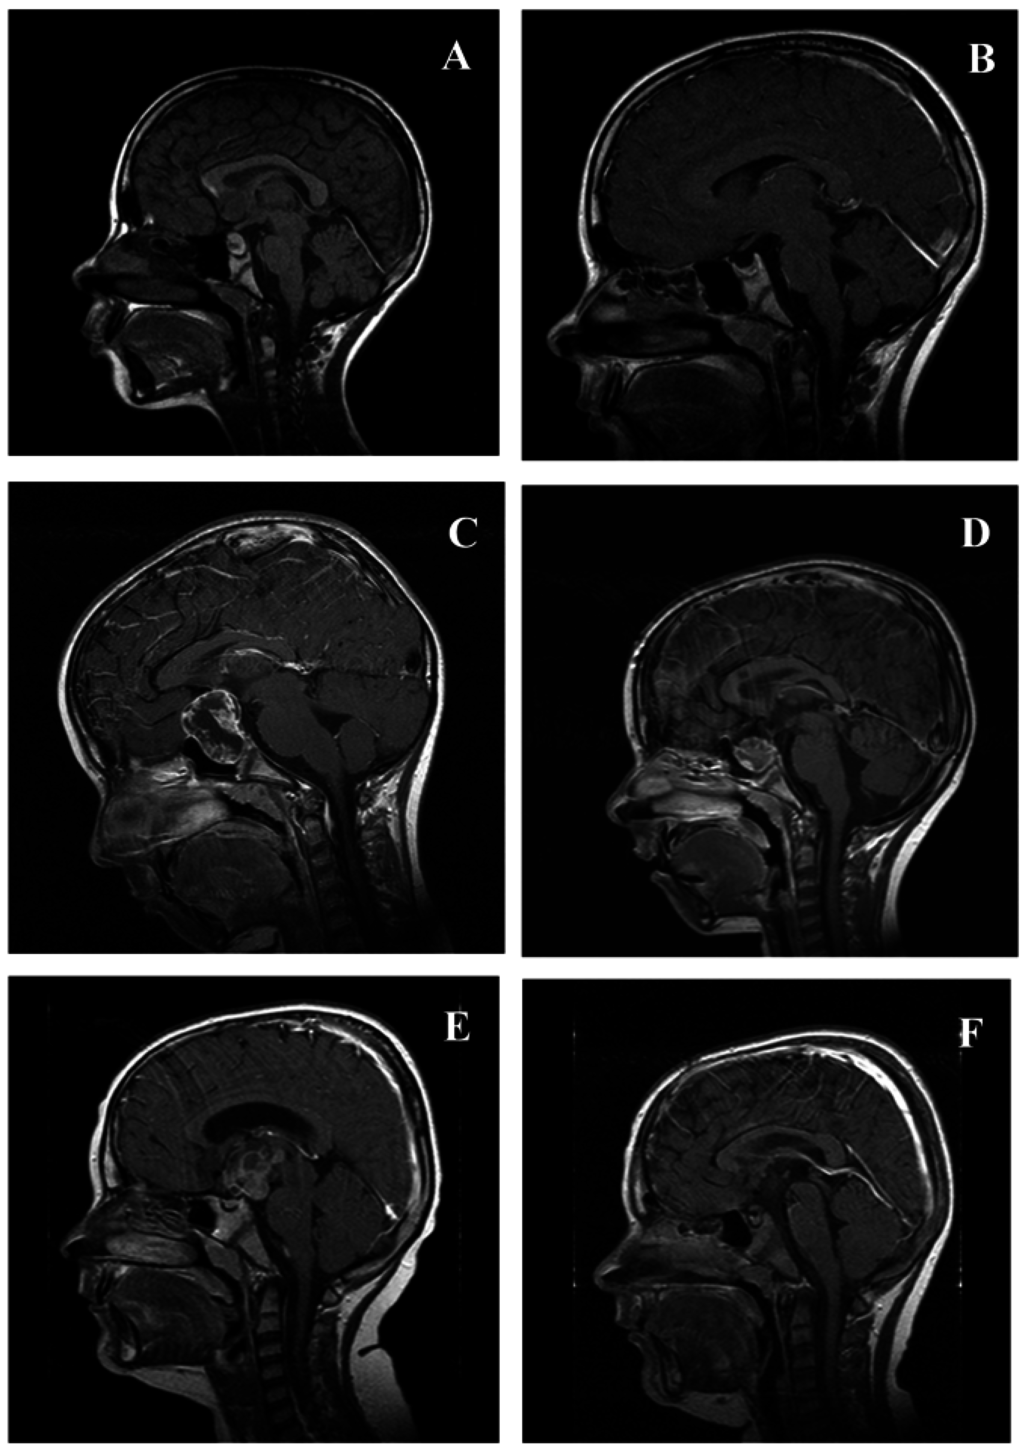

4. Imaging Studies